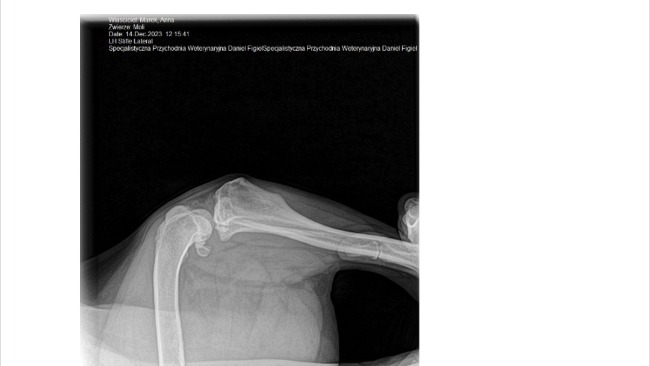

Stwierdzono u niej kulawiznę, bolesność kolana, zmiany zwyrodnieniowe stawu kolanowego, zmiany zwyrodnieniowe lewego łokcia- dysplazję. Konieczna jest operacja. Niestety koszt zabiegu to ponad 4000 zł, co przekracza moje możliwości finansowe. 😭😭😭